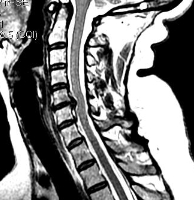

При шейном остеохондрозе грыжи не приводят к головным болям, они вызывают корешковый синдром, приводящий к болям и неприятным ощущениям (парестезии, слабости) в руке со стороны грыжи. Редко грыжа сдавливает спинной мозг или нарушает кровоснабжение его участка, приводя к миелопатии. Головные боли при остеохондрозе обусловлены нестабильностью в шейном отделе и болезненным напряжением мышц.

МРТ. Т2-зависимая томограмма. Сагиттальный срез. Грыжа диска.